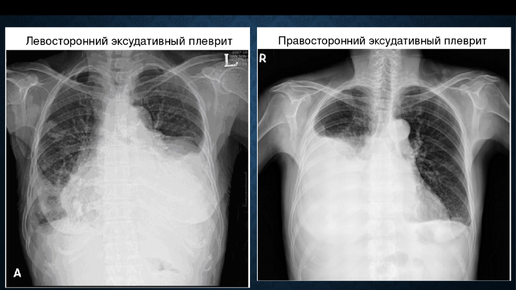

Лучевая диагностика гидроторакса